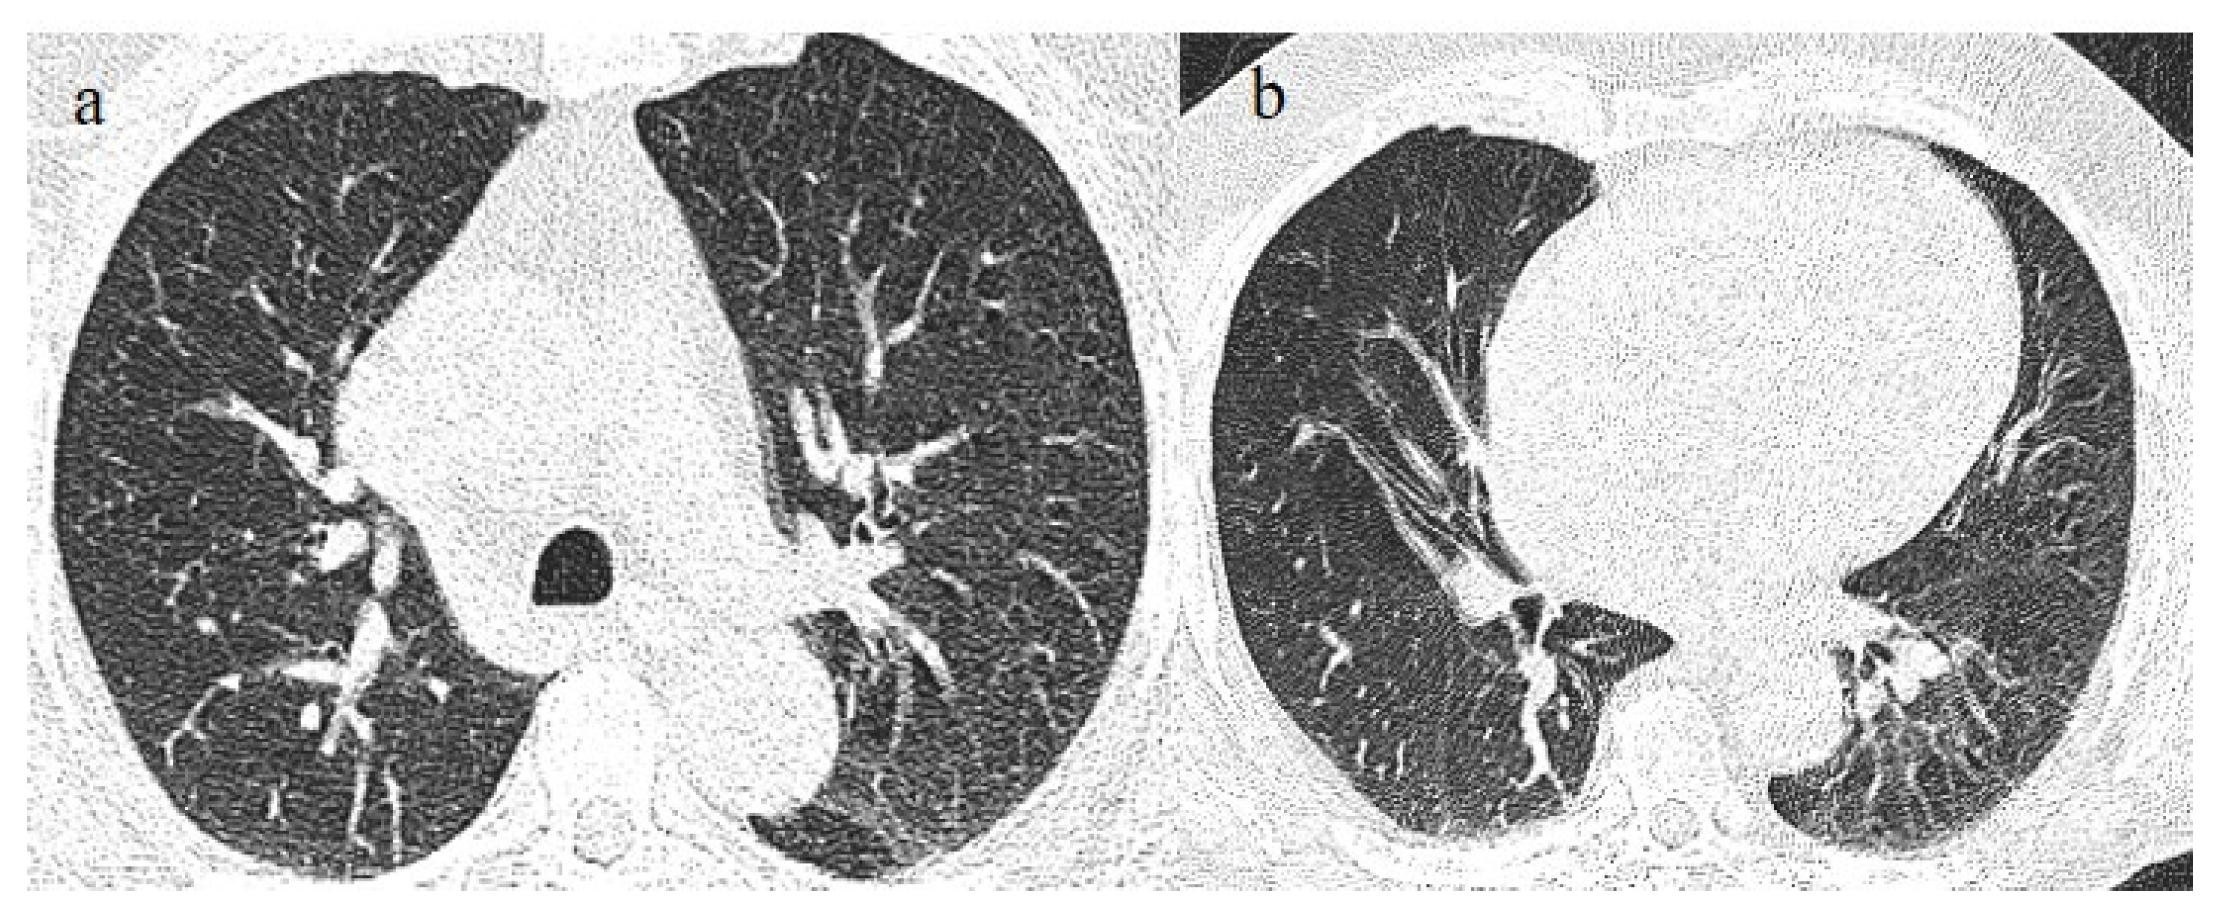

- Brogna, B.; Bignardi, E.; Brogna, C.; Capasso, C.; Gagliardi, G.; Martino, A.; Musto, L.A. COVID-19 Pneumonia in Vaccinated Population: A Six Clinical and Radiological Case Series. Medicina 2021, 57, 891. [Google Scholar] [CrossRef]

- Wada, N.; Li, Y.; Hino, T.; Gagne, S.; Valtchinov, V.I.; Gay, E.; Nishino, M.; Madore, B.; Guttmann, C.R.; Bond, S.; et al. COVID-19 Vaccination reduced pneumonia severity. Eur. J. Radiol. Open 2022, 9, e100456. [Google Scholar] [CrossRef]

- Granata, V.; Fusco, R.; Villanacci, A.; Magliocchetti, S.; Urraro, F.; Tetaj, N.; Marchioni, L.; Albarello, F.; Campioni, P.; Cristofaro, M.; et al. Imaging Severity COVID-19 Assessment in Vaccinated and Unvaccinated Patients: Comparison of the Different Variants in a High Volume Italian Reference Center. J. Pers. Med. 2022, 12, 955. [Google Scholar] [CrossRef] [PubMed]

- Lee, J.E.; Hwang, M.; Kim, Y.-H.; Chung, M.J.; Sim, B.H.; Chae, K.J.; Yoo, J.Y.; Jeong, Y.J. Imaging and Clinical Features of COVID-19 Breakthrough Infections: A Multicenter Study. Radiology 2022, 303, 682–692. [Google Scholar] [CrossRef]

- Verma, A.; Kumar, I.; Singh, P.K.; Ansari, M.S.; Singh, H.A.; Sonkar, S.; Prakash, A.; Ojha, R.; Shukla, R.C. Initial comparative analysis of pulmonary involvement on HRCT between vaccinated and non-vaccinated subjects of COVID-19. Eur. Radiol. 2022, 32, 4275–4283. [Google Scholar] [CrossRef]